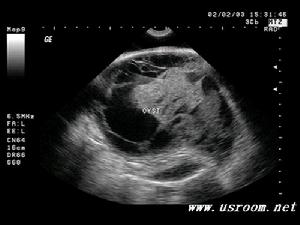

心包內惡性畸胎瘤X光圖早期病人無明顯臨床症狀,不易診斷。如出現胸部不適或心前區刺痛,心電圖僅提示心率異常無特異性。普通胸片檢查常因腫瘤與心臟影像重疊可造成漏診或誤診。近年來影像學發展迅速,現代化的高科技影像設備和技術已經成為心包內畸胎瘤診斷的主要檢查手段超聲心動描記或攝影心血管螢光電影照像術以及放射性核素掃描等綜合檢查,可以發現心包內腫塊的密實影像或回聲以及大量的心包腔積液。計算機中軸體層攝影(CT)對不同密度的組織如脂肪、水軟組織、骨骼的高解析度使心包內畸胎瘤的術前診斷成為可能磁共振成像(MRI),利用心血管中血液的流空效應也對本病的診斷很有意義。